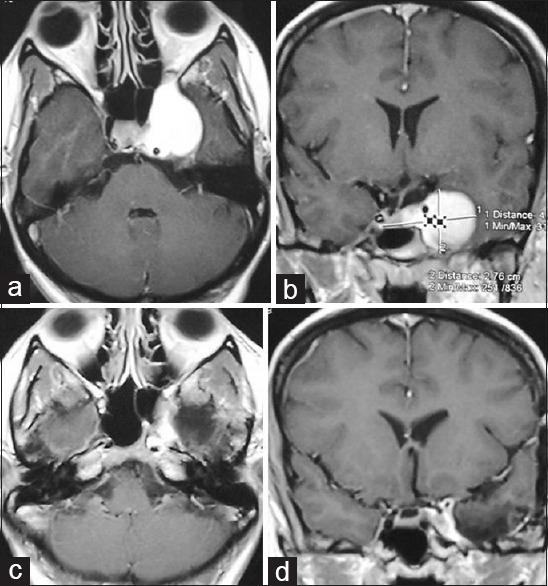

Total number of patient was 12. Patient's age range was 30-60 years. Follow-up range was 60 months to 19 months. Three was nonneoplastic lesion (tuberculosis, inflammatory and nonneoplastic lymphoid infiltration). Among the 9 neoplastic lesions, two hemangiomas, two meningiomas, three 6 nerve schwannomas, one osteoclastoma and one epidermoid tumor. Middle cranial fossa-subtemporal extradural approach was used in 9 cases and in two cases extended middle fossa zygomatic approach. New postoperative 3 nerve palsy developed in 5 cases all recovered completely except one. In seven patients 6 nerve palsy developed after operation; only one recovered. Postoperatively simultaneous 3, 4 and 6 nerve palsy developed in four cases. One interesting postoperative complaint of feeling of tickling down of warm water under the skin of left sided forehead was found in the patient of inflammatory disease of CS. Mortality was nil. Total resection was done in 9 cases. There was no recurrence till last follow-up.

患者总数为12例。患者年龄范围为30至60岁。随访时间为60个月至19个月。有3例为非肿瘤性病变(结核、炎症和非肿瘤性淋巴浸润)。在9例肿瘤性病变中,有2例血管瘤、2例脑膜瘤、3例6神经鞘瘤、1例骨巨细胞瘤和1例表皮样肿瘤。9例采用中颅窝 - 颞下硬膜外入路,2例采用扩大中颅窝颧骨入路。术后新出现3神经麻痹5例,除1例未完全恢复外其余均完全恢复。7例患者术后出现6神经麻痹;仅1例恢复。术后4例同时出现3、4和6神经麻痹。在CS炎性疾病患者中发现了一种有趣的术后主诉,即左侧前额皮肤下有温水向下挠痒的感觉。无死亡病例。9例实现了全切除。至最后一次随访时无复发。